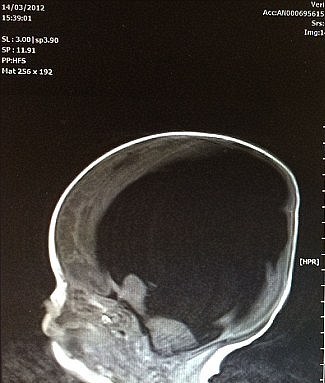

A 6-year-old boy from Abbeytown, Cumbria, has defied all odds after thriving despite being born with only 2% of his brain.

The mother of the ‘miracle’ baby, Shelly Wall, has spoken out and explained that her son developed hydrocephalus, a rare condition that affects the brain when he was still in the womb.

When Noah was born, he only had 2% of his brain and the family was worried about his development. Over the span of several years, however, Noah’s brain miraculously kept on growing and so did the boy.